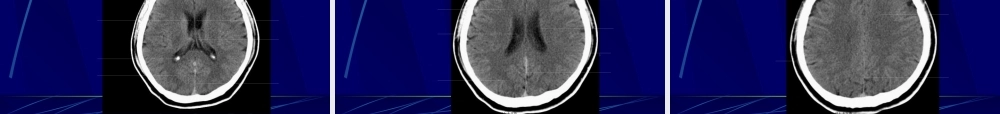

中枢神经系统正常及异常影像改变北京协和医院放射科第一页,共七十八页。中枢神经系统影像学技术颅骨平片脑血管造影脑CT脑磁共振第二页,共七十八页。头颅平片〔正侧位像〕第三页,共七十八页。头颅平片诊断价值有限•观察异物的存在和骨质结构的明显变化•显示骨折、肿瘤骨转移、网状内皮系统疾病、代谢性骨病、骨纤、畸形性骨炎等•观察颅骨骨折,有学者建议直接行CT•注意区分正常颅缝、血管沟和骨折线•有时可看见颅内钙化,如松果体钙化、肿瘤钙化等(中线钙化:松果体钙化、第三脑室脉络丛钙化、大脑镰钙化)•侧位可观察蝶鞍的形态,如扩大提示垂体瘤等,但不扩大也不能排除病变第四页,共七十八页。脑血管造影第五页,共七十八页。脑血管造影适应征•诊断脑动脉瘤、血管发育异常、血管闭塞•了解脑肿瘤的供血动脉•可同时行介入治疗•溶栓•Coil〔螺圈〕闭塞动脉瘤和血管畸形等•术前栓塞富血管性肿瘤如脑膜瘤•其他第六页,共七十八页。第七页,共七十八页。NeuroCT----CT在CNS的应用•CT平扫•疑心急性颅内出血的首选检查手段•假设CT已有堵塞征象,那么不应系统溶栓•CT血管造影〔CTangiography,CTA)•识认血管•其他最新应用•CT脑灌注成像〔CTperfusion)第八页,共七十八页。MRItips•主要基于3个可变的生物学参数:•质子密度〔protondensity〕•纵向驰豫恢复时间〔T1relaxationtime)•横向驰豫恢复时间〔T2relaxationtime)•通过采用不同的脉冲序列和不同的成像参数,获得反映上述生物学参数比照的MR图像,即质子密度加权像〔PDWI)、T1加权像〔T1WI)和T2加权像〔T2WI)•这些图像上的信号强度与特定的组织特征有关。•比方:血肿的化学和物理结构随时间而变化,直接影响其MR图像的信号强度•由此提供出血时间的信息,急性?亚急性?还是慢性?第九页,共七十八页。其他方法•气脑造影及脑池造影Airencephalographyandcisternography•有创性检查,现已根本不用。•USG•用于囟门未闭的婴幼儿,观察脑内结构;•TCD:检测颈部及颅内动脉血流动力学变化,了解头颈部血管病变的情况。第十页,共七十八页。PartII:imagingfeatures中枢神经系统正常及异常影像学表现第十一页,共七十八页。MRI图像T1加权像:--看正常解剖---脑脊液和房水是黑的灰质比白质暗〔就像真的〕T2加权像:--看病理改变---脑脊液和房水是白的灰质比白质亮第十二页,共七十八页。骨皮质骨髓质脑膜脑脊液脑白质脑灰质血管T1WI低信号高信号低信号低信号高信号等信...